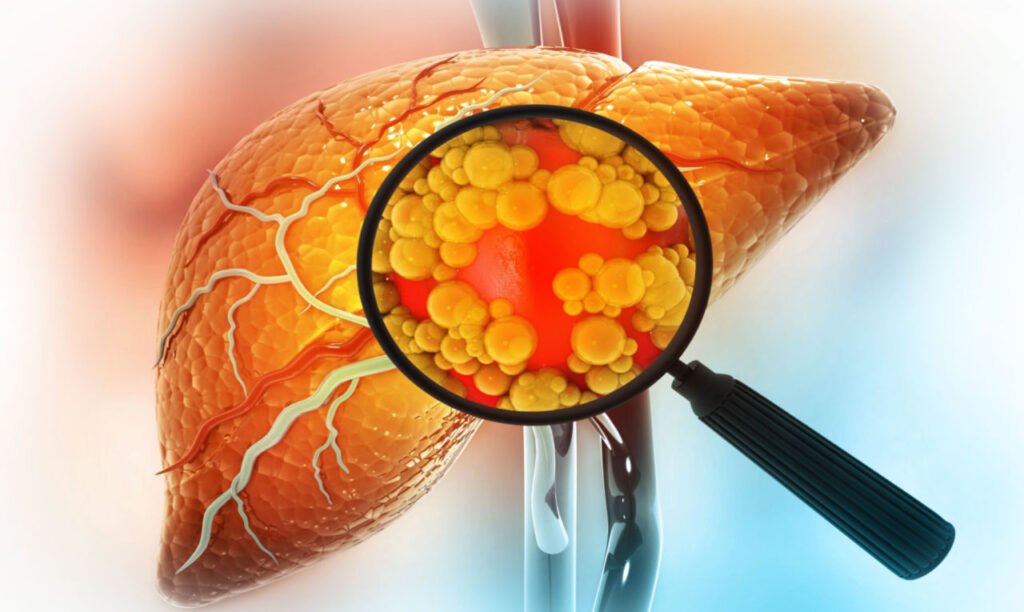

O fígado é o segundo maior órgão do corpo humano, e é, sem sombra de dúvidas, o mais importante para o funcionamento geral de nosso corpo.

É no fígado que acontece o armazenamento de todos os nutrientes vitais para o equilíbrio e bom funcionamento do organismo.

Se algo de errado acontece no fígado, todo o resto fica imediatamente comprometido.

Atualmente a maioria dos médicos vem indicando o uso de remédios farmacêuticos. Entretanto, esses remédios na verdade pioram o fígado mais que ajudam.

Isso acontece porque muitos desses medicamentos possuem substâncias que são tóxicas para o fígado, e acabam causando inflamação, lesão ou disfunção hepática.

Anti-Inflamatórios, Antidiabéticos e Analgésicos, causam efeitos colaterais para quem tem gordura no fígado como a diarreia, indigestão, úlcera, tontura, ganho de peso e vários outros efeitos colaterais.

Alguns médicos recomendam medicamentos em cápsulas, que também fazem mal ao fígado. Os produtos em cápsulas podem sobrecarregar o fígado devido à alta concentração de ingredientes ativos e ao metabolismo hepático, especialmente em pessoas com doenças hepáticas.

Para quem tem gordura no fígado, o ideal seria um tratamento em gotas 100% natural e eficaz, que não agrediria o fígado durante o processo de tratamento.